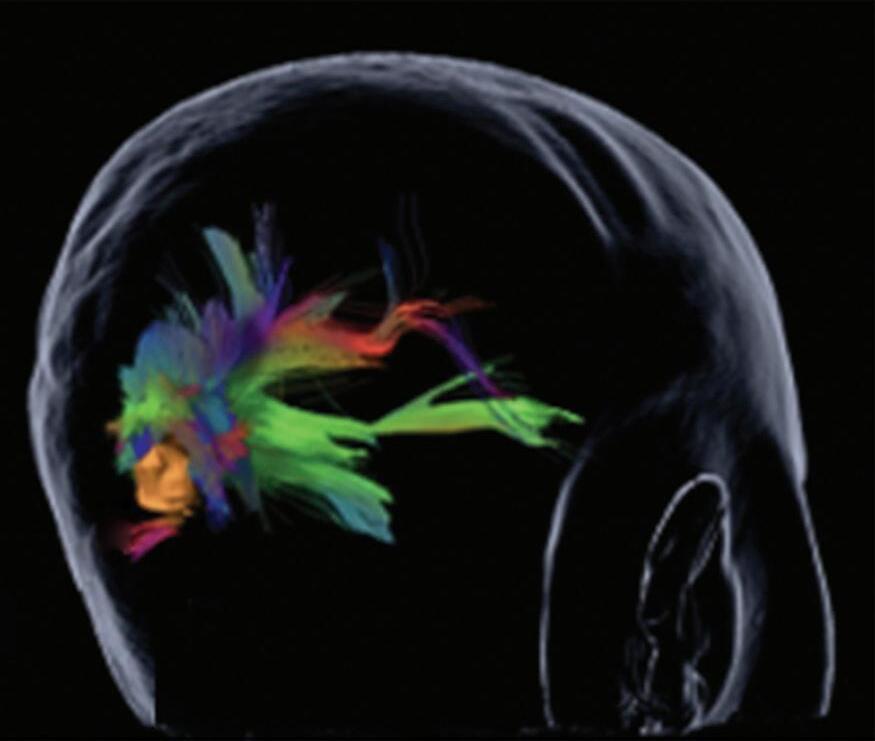

A utilização de técnicas avançadas, como a tractografia (Fig. 1-23), reconstruções 3D, permitem um estudo detalhado de estruturas anatômicas e sua relação com as patologias cerebrais, facilitando assim o planejamento cirúrgico. A tractografia, uma técnica de ressonância magnética, permite estudar os tratos da substância branca do cérebro, mostrando sua posição, anatomia e integridade, por meio da análise do movimento das moléculas de água no tecido cerebral.35

tractografia cerebral, cortes axiais. A codificação de cores demonstra as fibras com orientação laterolateral em vermelho, a orientação anteroposterior em verde e a craniocaudal em azul. Observe o deslocamento das fibras de associação (verde) no lobo temporal esquerdo em relação à MAV.